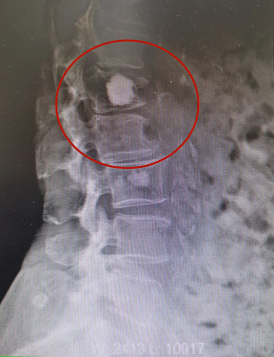

患者骨水泥椎体成形术术前影像

患者孙某某,女,83岁,早上晨练后摔伤出现腰背部疼痛,起立行走困难,在家卧床休息7小时后疼痛未缓解,来院门诊行腰椎X光片检查后提示:腰L1椎体压缩性骨折,告知患者及其家属诊疗方案后,患者及其家属要求手术治疗。入院第二天予患者行腰L1骨水泥椎体成形术,术后当天患者自觉胸腰背部疼痛明显缓解,术后第二天患者下床自行活动良好。